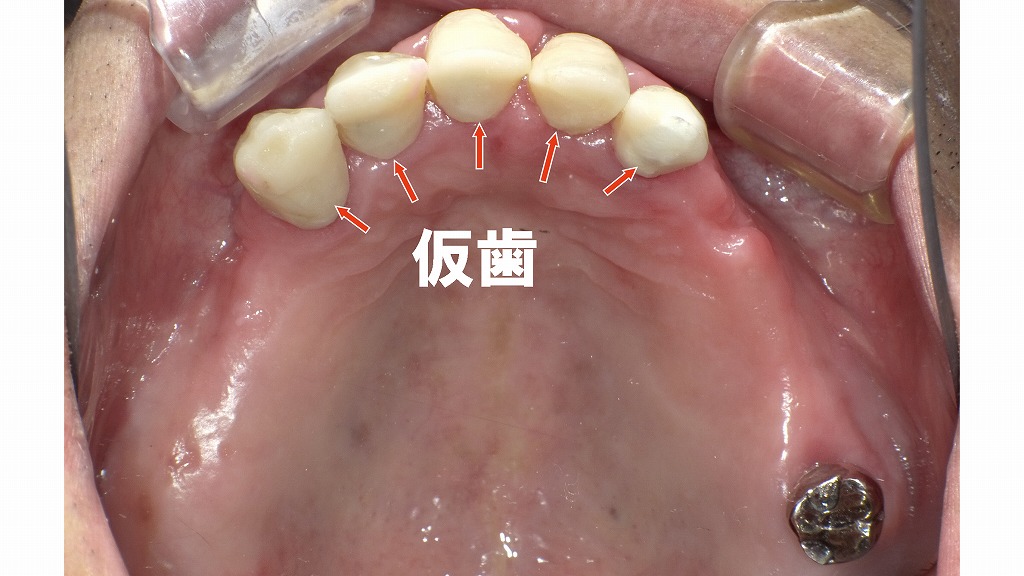

上顎咬合面観による詳細評価と保存可能歯の判定

この画像は、**上顎の咬合面観(上から見た状態)**です。上顎歯列全体にわたり重度のう蝕が進行しており、歯冠崩壊が顕著です。以下に詳細な観察と、保存可能歯の判定を示します。

🦷 全体所見

- 全歯にう蝕が見られ、広範囲に黒褐色化・崩壊しています。

- 歯冠が大部分失われ、残根状態の歯が多く存在。

- 歯列弓は不完全で、咬合支持がほぼ喪失しています。

- 歯肉は炎症性変化を伴い、一部では歯肉退縮も確認できます。

🦷 各部の詳細評価(保存可否の目安)

| 部位 | 現状所見 | 診断・処置内容 | 保存可否 |

|---|---|---|---|

| 右上3番(犬歯) | 歯冠崩壊は中等度。根の長さ十分で歯周支持も残存。 | 再根管治療により感染除去し、支台歯として利用可能。 | 保存可 |

| 右上2番(側切歯) | 歯冠欠損大だが、根尖病変軽度。 | 再根管治療により保存可能。支台築造後、前装冠修復予定。 | 保存可 |

| 右上1番(中切歯) | う蝕が深部まで進行しているが、歯根は健全。 | **抜髄処置(根管治療)**を行えば支台歯として機能可能。 | 保存可 |

| 左上1番(中切歯) | 既存根管治療あり。感染再発あり。 | 再根管治療により感染源除去し、修復可能。 | 保存可 |

| 左上2番(側切歯) | 生活歯で深いう蝕。根尖病変なし。 | **抜髄処置(根管治療)**により支台歯として再利用可。 | 保存可 |

| 左上3番(犬歯) | 歯冠・根ともに崩壊進行。歯槽骨吸収も高度。 | 残存根長不足のため支台歯として不適。 | 保存不可(抜歯) |

| 左上7番(第二大臼歯) | 根管充填不良、二次カリエスあり。 | 再根管治療により感染除去後、クラウン修復で保存可能。 | 保存可 |